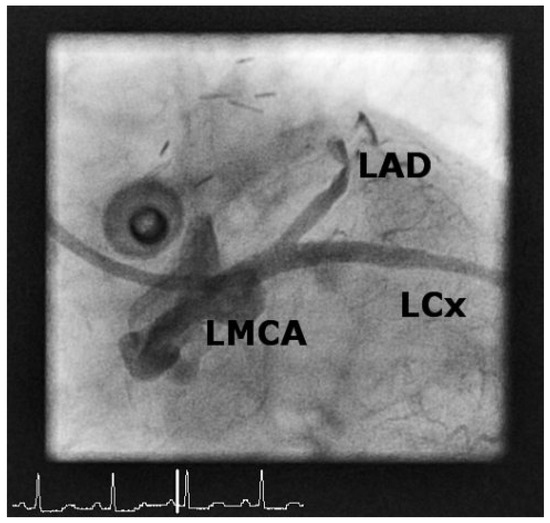

Case 1